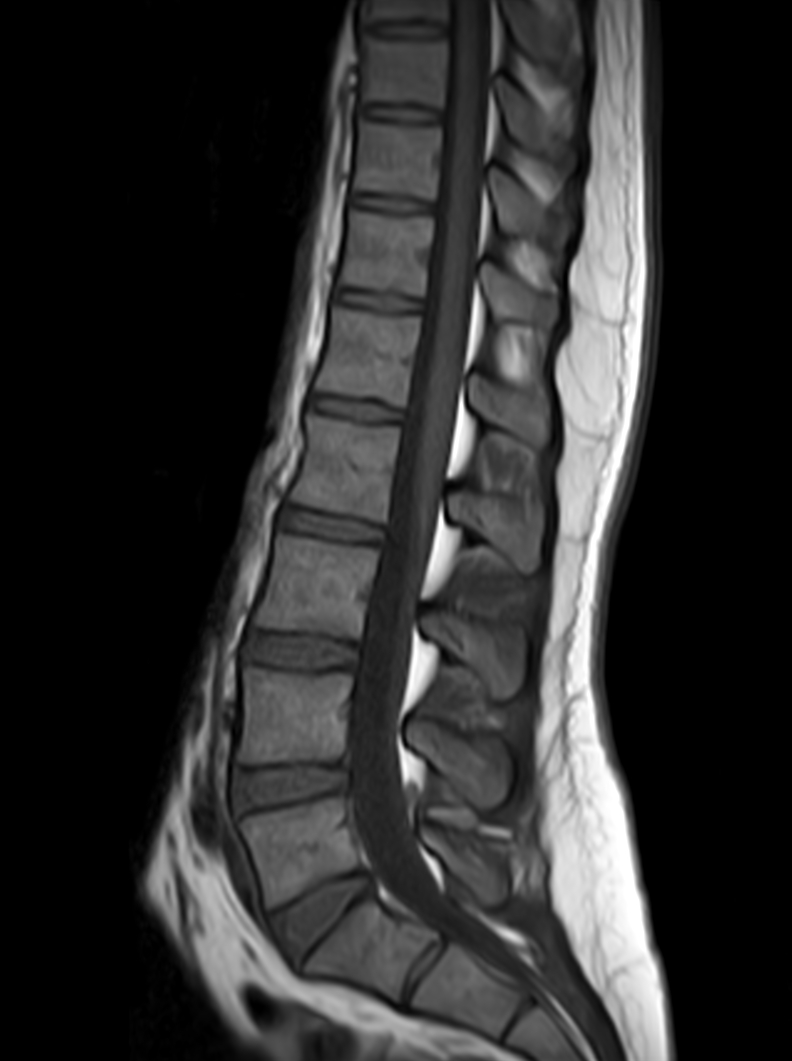

Sagittal mDIXON XD - T2w TSE (Water only)